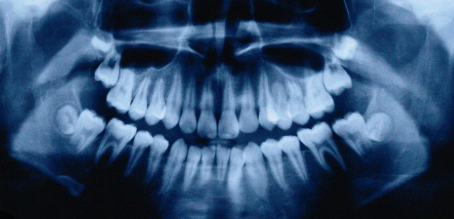

치아가 빠진 자리의 잇몸뼈는 마치 사용하지 않는 근육이 줄어드는 것처럼, 시간이 지날수록 급격히 감소합니다.

특히 발치 후 1년 동안 가장 빠르게 뼈가 줄어들어, 이후 임플란트 시술이 훨씬 더 복잡해질 수 있습니다.

잇몸뼈가 부족해지면 임플란트 식립을 위해 뼈 이식이 추가로 필요할 수 있습니다.